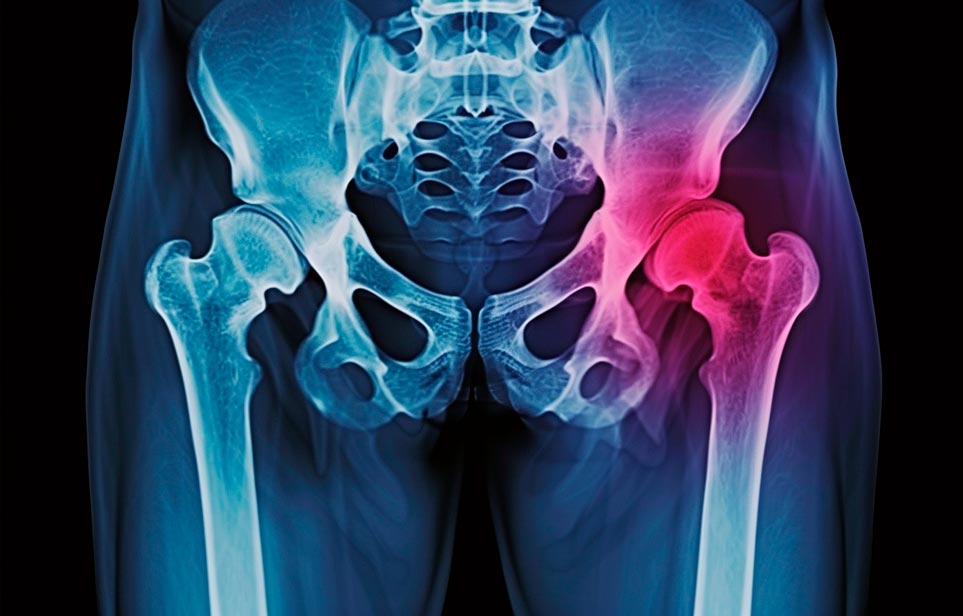

Реабилитация пожилых после перелома шейки бедра в Губкине

Эффективная и профессиональная реабилитация после перелома шейки бедра в Губкине осуществляется по демократичным ценам лучшими специалистами современной медицинской клиники «Заботливые люди» с применением персонального подхода к каждому пожилому человеку с такой тяжёлой травмой бедренной кости ноги. В процессе осуществления такой специализированной услуги все наши пациенты имеют возможность получения качественного и достойного обслуживания, эффективного восстановления. Лучший дом престарелых позаботиться о Вашем близком человеке.

Такая травма в большей части случаев возникает у граждан преклонного возраста. При её появлении на протяжении длительного времени сохраняются болевые и неприятные ощущения в области паха, при которых серьёзно ухудшается качество жизни, возникает множество последствий для его жизни и здоровья.

По какой симптоматике можно определить перелом шейки бедра?

Выявить его можно по возникновению следующей тревожной симптоматики:

- Визуально повреждённая нога сокращается на несколько сантиметром из-за сокращения мышц.

- Стопа выворачивается наружу.

- В лежачем положении человек не может поднять ногу.

При такой симптоматике важно незамедлительно обращаться к специалистам для получения всей необходимой помощи, терапии и восстановления после перелома шейки бедра. Если не оказать помощи старику, то это приведёт к гноению, инвалидности, иным видам осложнений.